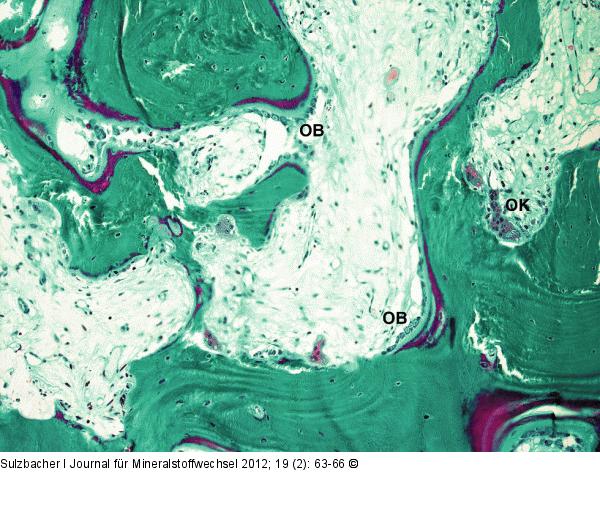

Abbildung 1: Lamellenknochen - Osteoblasten In der Goldner-Färbung am unentkalkten Knochenmaterial zeigt sich ein reifer Lamellenknochen grün und das von Osteoblasten (OB) in eine Lakune deponierte Osteoid rot. Zusätzlich typische Riesenosteoklasten (OK) in einer tiefen Lakune (Vergrößerung × 200). |